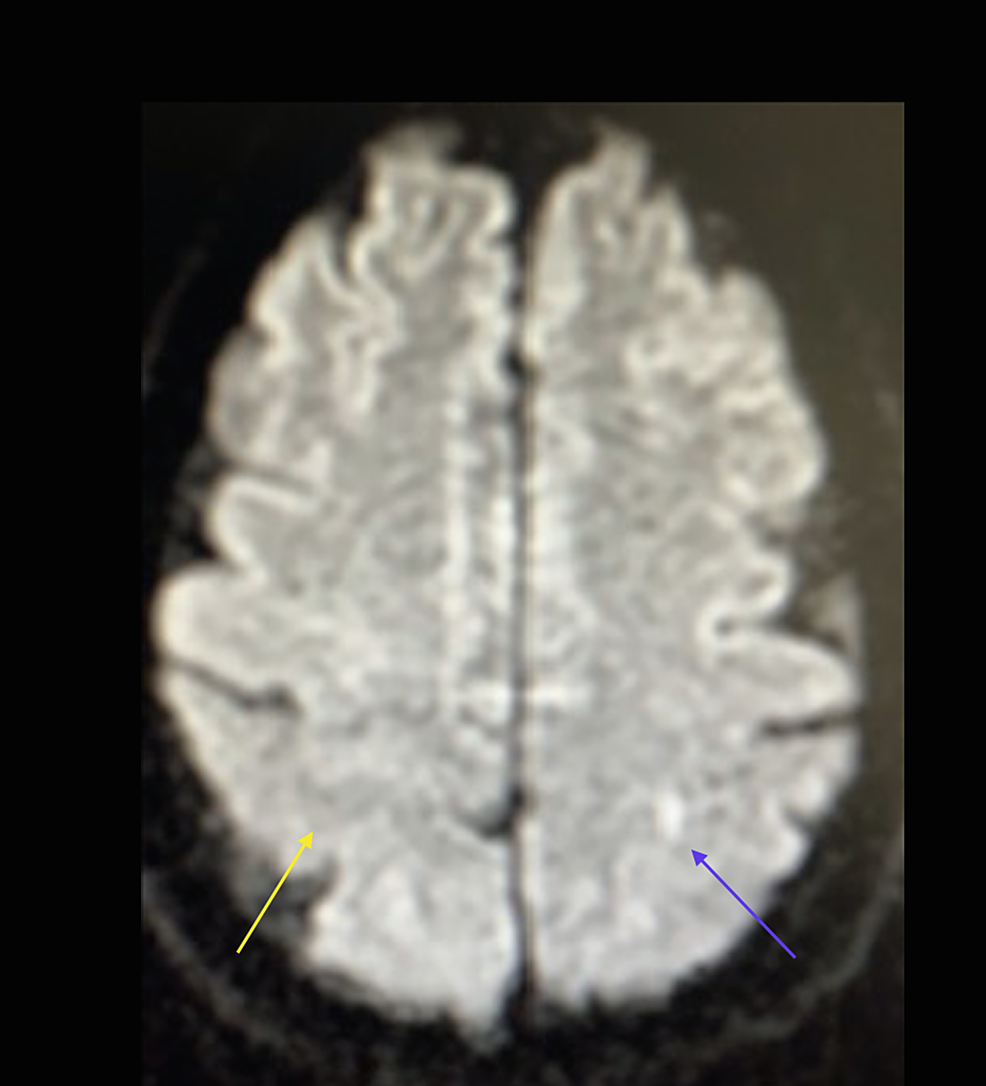

From www.cureus.com